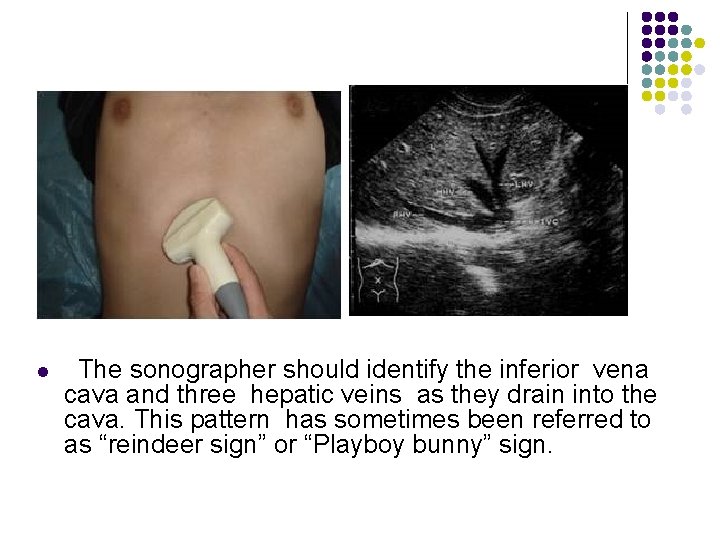

Transverse Scan Plane l Scan Ⅰ The initial transverse scan is made with the transducer under the costal margin at a steep angel perpenducular to the diaphragm. The patient should be in deep inspiration to adequately record the dome of the liver. The sonographer should identify the inferior vena cava and three hepatic veins as they drain into the cava. This pattern has sometimes been referred to as “reindeer sign” or “Playboy bunny” sign.

l The sonographer should identify the inferior vena cava and three hepatic veins as they drain into the cava. This pattern has sometimes been referred to as “reindeer sign” or “Playboy bunny” sign.